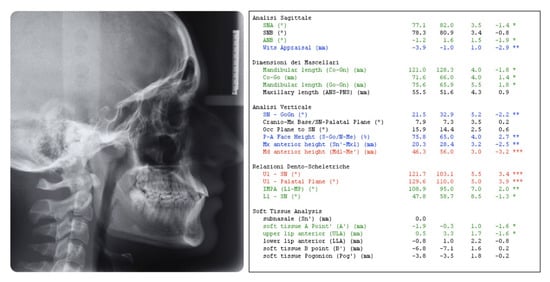

2.1. Diagnosis and Etiology